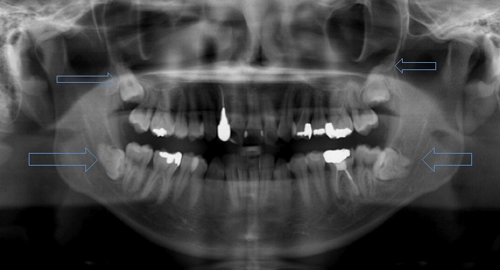

平沢歯科では、インプラント治療の成功率を高めるために、CTを活用した精密な診査・診断を行います。骨の厚みや神経の位置を正確に把握し、患者様に適した治療計画を立てたうえで施術を行います。また、日本口腔インプラント学会専修医の資格を持つ院長が、長年の経験と技術を活かし、安全に配慮した治療を提供します。